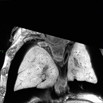

| Mutant 012-003-2 (E16.5) presents with PTA | Cplane1b2b012Clo/Cplane1b2b012Clo | C57BL/6J-Cplane1b2b012Clo |

| Mutant 012-003-2 (E16.5) has hypoplastic lungs | Cplane1b2b012Clo/Cplane1b2b012Clo | C57BL/6J-Cplane1b2b012Clo |